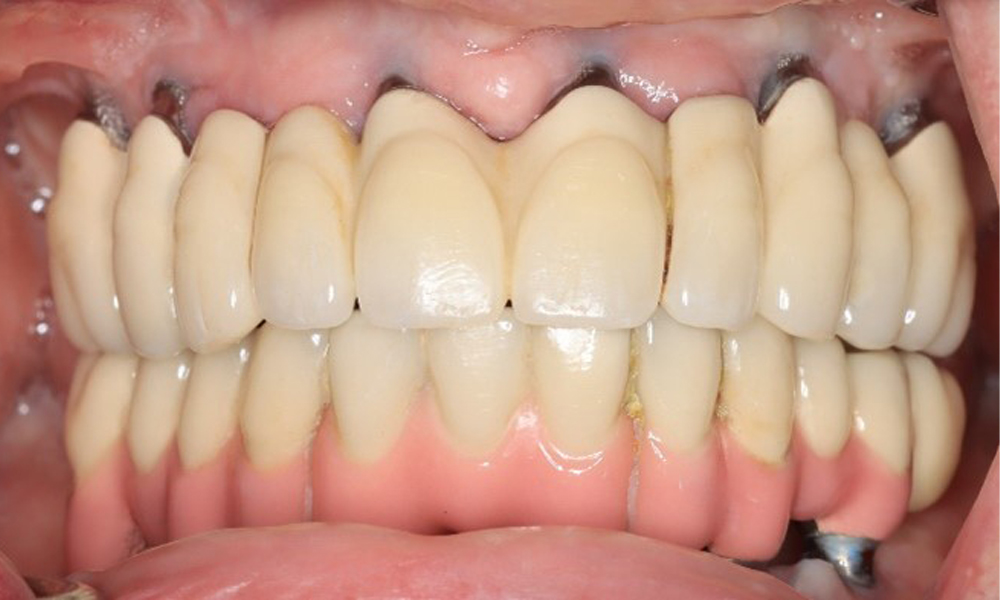

A 74-year-old patient presents for a consultation. The anamnesis shows that the patient has well-controlled hypertension and is taking Lixiana. Additionally, the patient had a kidney carcinoma in 2020. The patient’s lifestyle is unremarkable. She has no natural teeth left and has six implants in both the upper and lower jaws, which are fitted with crowns or bridges. Current findings show no peri-implant mucositis or peri-implantitis; however, there are occasional minor bleeding at the implant sites.

Provisions: Implants in regions 011, 013, 015, 021, 023, 025, 031, 033, 035, 042, 044, 046

The peri-implant situation is currently stable. Due to the complexity of the superstructures, the patient has a moderate risk of development and a low risk of progression for peri-implant diseases.